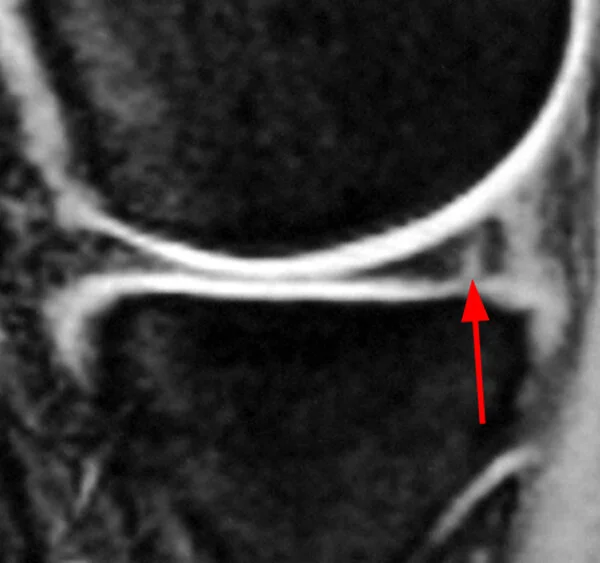

- MRI: gold Standard

Radial tear

Horizontal tear

longitudinal vertical tear